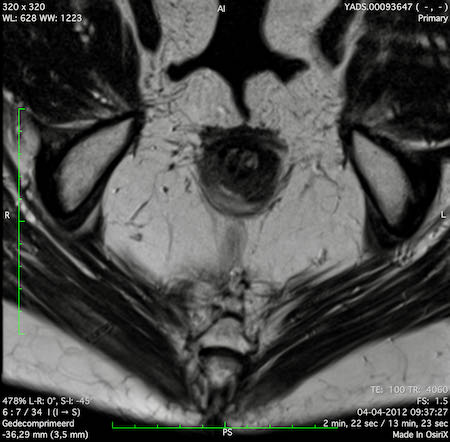

Hình ảnh

Các hình ảnh được cung cấp cho thấy ung thư biểu mô tế bào nhẫn với tình trạng dày lan tỏa thành trực tràng, hình ảnh bia bắn điển hình, và sự xâm lấn mỡ mạc treo trực tràng.